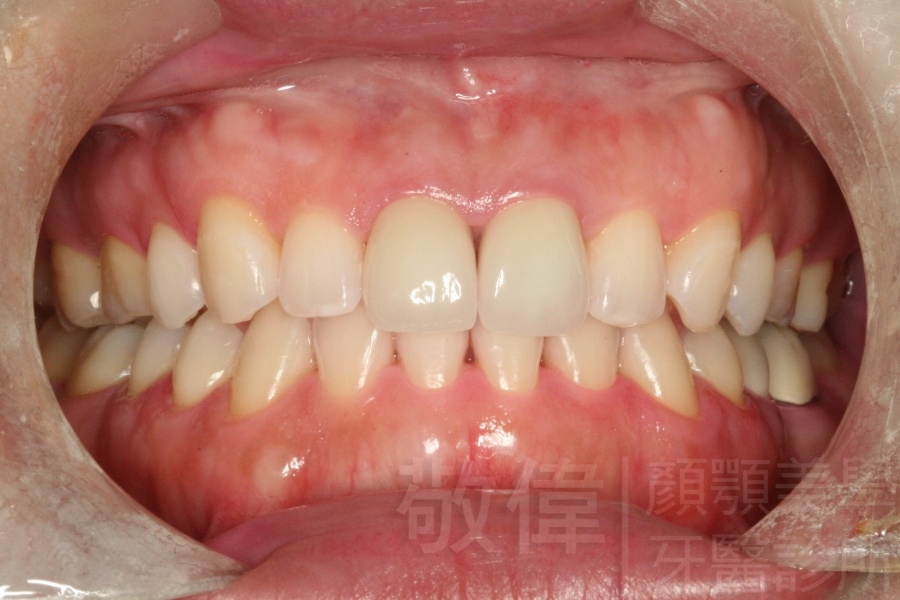

變臉矯正,原來戽斗妹跟大歪臉變成自信正妹

經由本院3D數影X光影像儀分析、與3D齒顎顏矯正技術,再配合口腔顎面正顎專科醫師施以正顎手術治療,雙方共同合作,使患者臉部外觀有很好的改善,大歪變小歪,產生了天南地北的大改變,她的人生也整個變得不一樣。

因為矯正與正顎手術的配合,使「戽斗妹」變成了「陽光正妹」,完全的改變了她的人生,在面對各種場合、與人交際都散發出自信微笑。所以,奉勸家長,如果小朋友有臉顎畸型的問題,應該考慮配合做這種簡單、安全、有效的正顎手術。

「3D齒顎顏矯正」,不止矯正您的牙齒,也會改變您的人生。「治療前」和「治療後」出社會的人生際遇一定會截然不同。